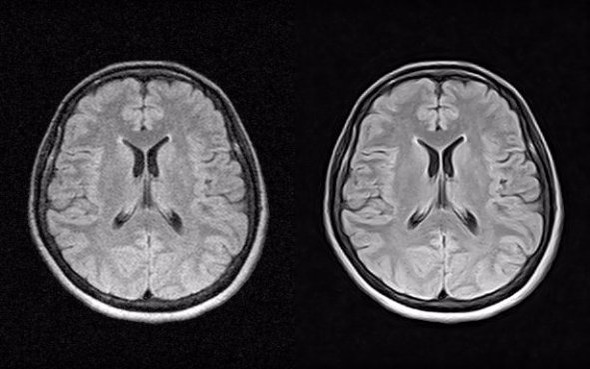

AcuImages' algorithms and software dramatically improve diagnostic confidence in almost all medical imaging modalities,

which includes but not limited to:

Original Enhanced